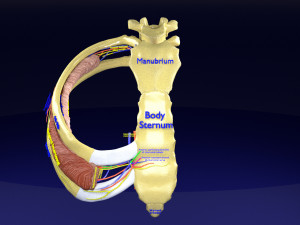

The model meshes include adult circulation versus circulation in Tetralogy of Fallot (TAF), arrow labels and text labels. The blood flow in a patient with Tetralogy of Fallot is outlined in this model. To contrast it to normal blood circulation a separate model of normal circulation is included. The Tetralogy of Fallot (OVER RIDING OF AORTA, PUL STENOSIS, VENTRICULAR SEPTAL DEFECT, RIGHT VENTRICULAR HYPERTROPHY), fossa, ligament teres , venosus, and arteriosus are duly depicted with proper labelling and blood flow directional arrows. Excellent model for teaching, demonstration and knowlegde of human body. The models include both procedural and image textures blend files separately. The texture file include diffuse, roughness and normal png and jpeg based on non overlapping UV maps.